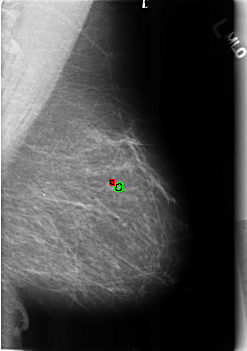

B_3217_1.LEFT_MLO

LEFT_MLO LINES 4552 PIXELS_PER_LINE 3208 BITS_PER_PIXEL 12 RESOLUTION 50 OVERLAY

FILE: B_3217_1.LEFT_MLO.OVERLAY

TOTAL_ABNORMALITIES 2

ABNORMALITY 1

LESION_TYPE CALCIFICATION TYPE COARSE-LUCENT_CENTER DISTRIBUTION N/A

ASSESSMENT 2

SUBTLETY 3

PATHOLOGY BENIGN_WITHOUT_CALLBACK

ABNORMALITY 2